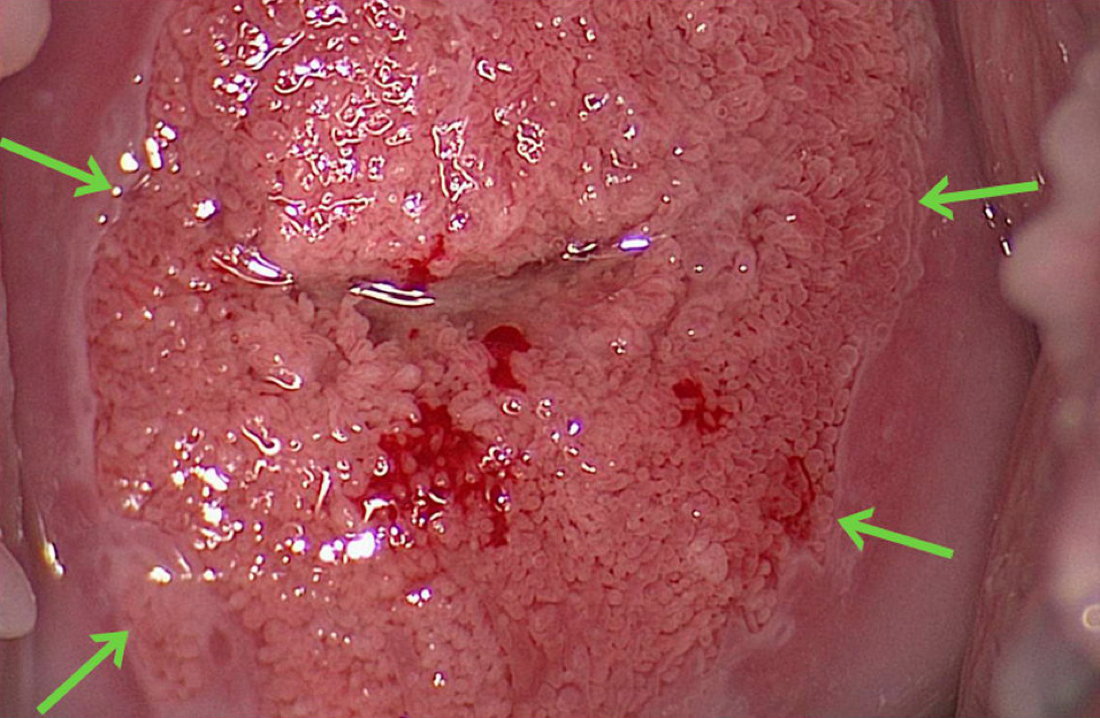

Cervical cancer and precancer originate at the squamocolumnar junction which is indicated by green arrows. Columnar epithelium borders directly on squamous epithelium.

The squamocolumnar junction can be the congenital or postpuberty junction. In this colposcopic image of an adolescent, the squamocolumnar junction is the congenital junction.